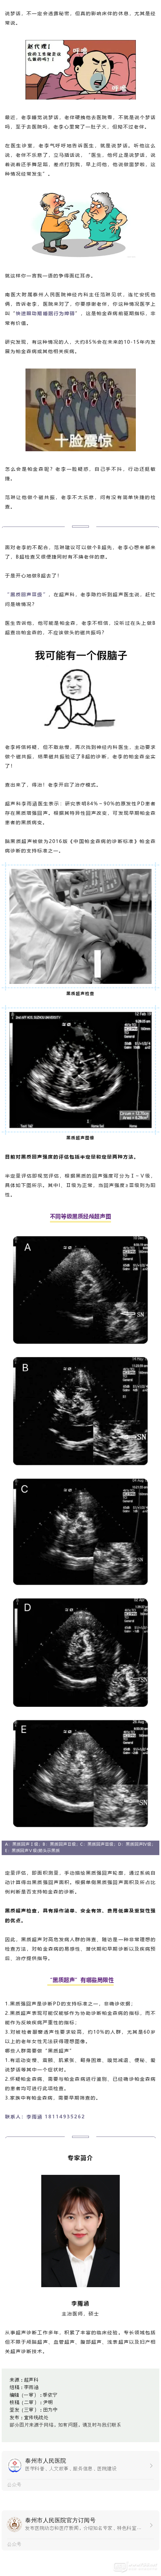

經(jīng)常說(shuō)夢(mèng)話,可能是這個(gè)病,去做個(gè)B超吧!